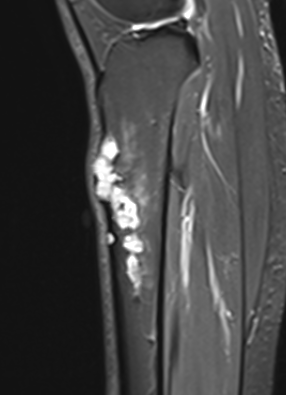

MRI

Khanna et al Skeletal Radiol 2008

- 24 cases of OFD / adamantinoma

- adamantinomas tend to be larger / cortical destruction / complete marrow involvement